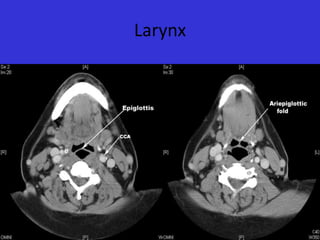

Larynx